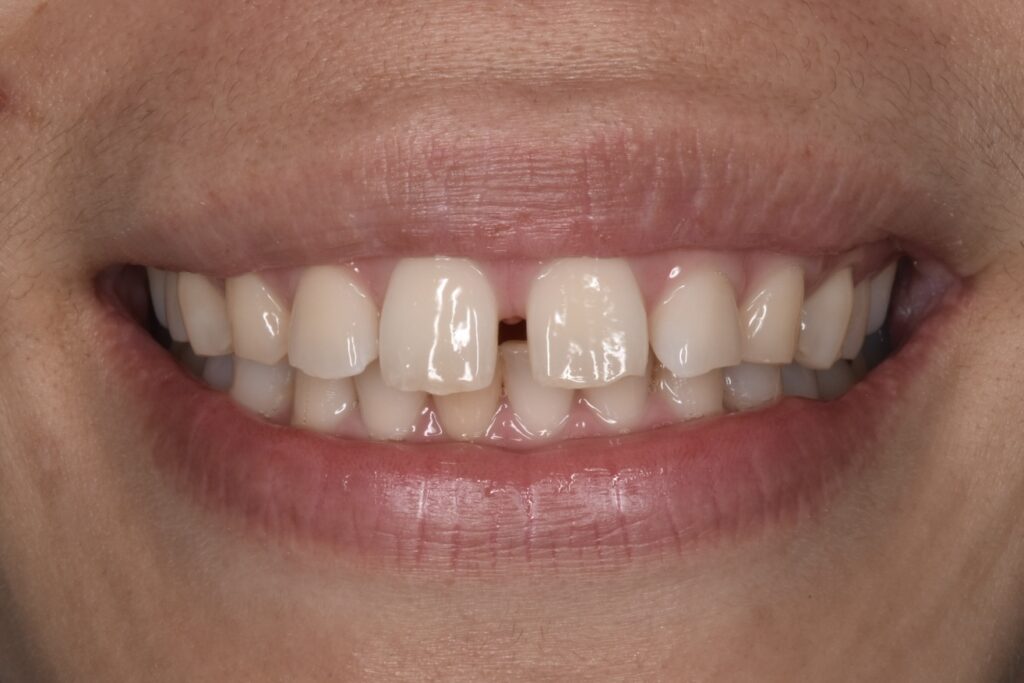

すきっ歯の改善を矯正治療でおこなった例です

モニター1 インビザラインライトプランで治療 治療期間14週間(約3・5ヶ月)

治療前